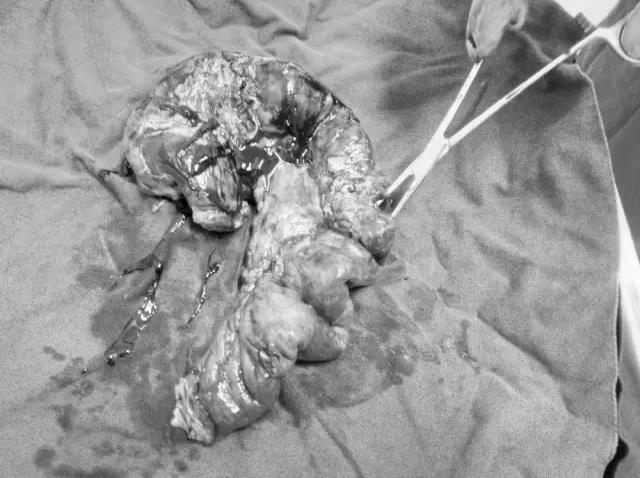

肠瘘段小肠标本,止血钳指示处为瘘口位置

5月27日上午9时,由崔小兵主任医师主刀、郭魁元副主任医师作为助手,在麻醉科、手术部的大力配合下剖腹探查。术中可见腹腔有约1000ml黄色稍混渗液,升结肠外侧结肠沟侧腹壁可见一缺损,回肠嵌顿于破口疝出皮下。此段嵌顿小肠近端梗阻,肠管弥漫性扩张,肠壁增厚,还纳小肠后,见腹壁有一约6cm大小破口,与皮肤溃破处相通,内可触及髂骨棘部分断裂及多个锐利骨碎片。疝出小肠约50cm,伴大量脓苔,且伴有血运障碍,可见一0.5cm破口,有肠液溢出。告知患者家属病情及手术方案征求家属同意后,决定行"肠瘘段小肠切除,回肠-横结肠吻合。关腹后,由骨科何江涛、王延明医师行“骨盆右侧粉碎性骨折局部坏死感染脓肿切开、扩大清创修复、筋膜组织瓣成形术”,术后在护理部精心护理下,患者恢复很快,已于6月9日康复出院。患者家属出院时激动的说,“骨折术后遭遇肠子破裂,原本觉得整个世界都塌了,经过你们的手术治疗,这么快就康复出院,让我们重获新生,由衷地感激郑州大学五附院。”